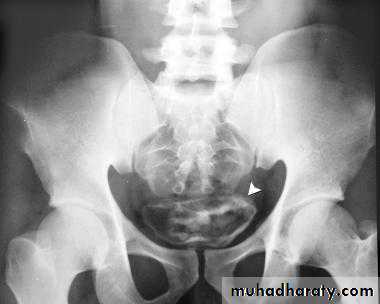

IVU

CT

cystoscope